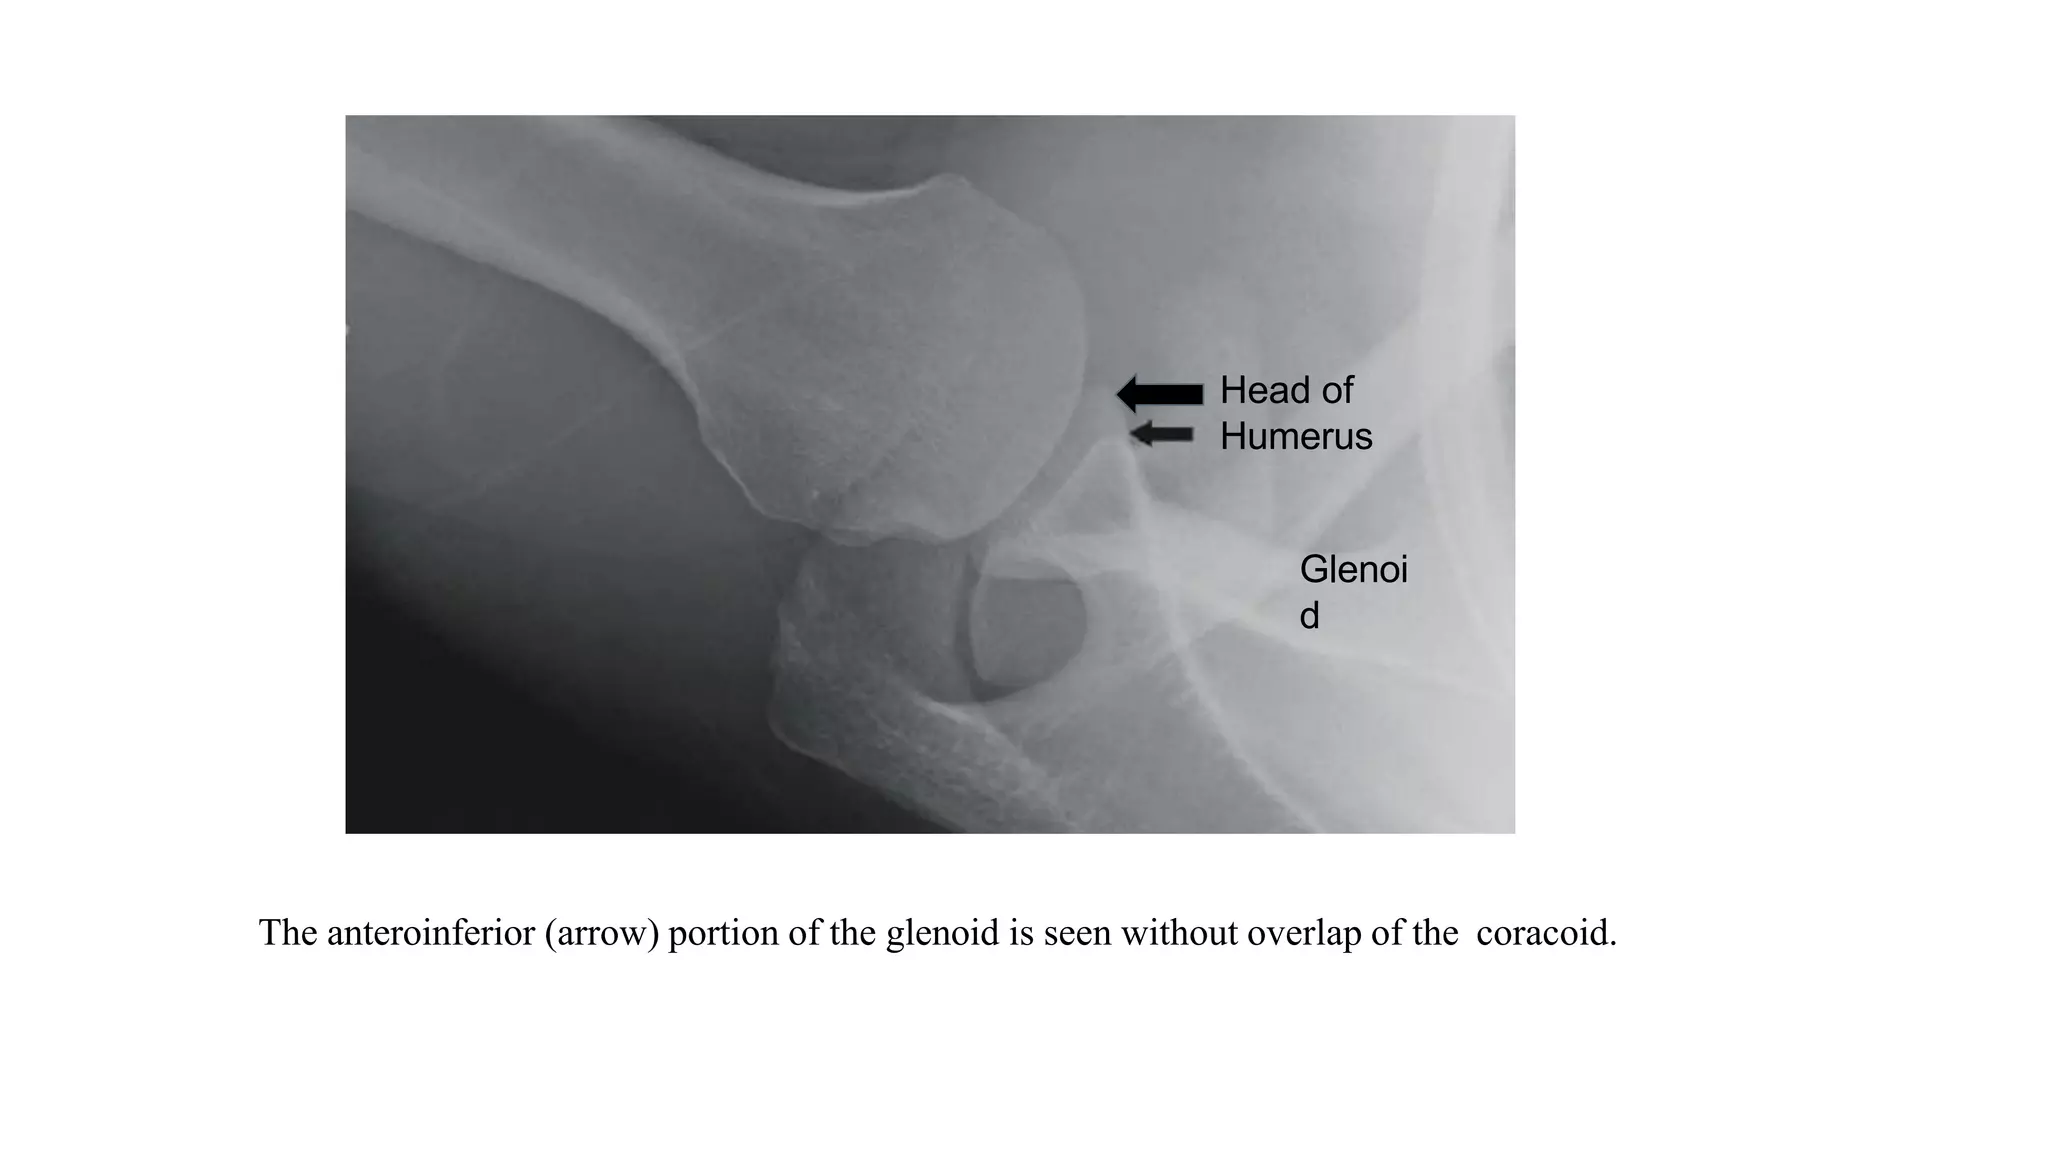

The anteroinferior (arrow) portion of the glenoid is seen without overlap of the coracoid.

Glenoi

d

Head of

Humerus